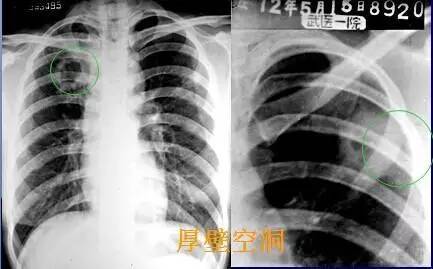

基础篇!肺部常见病变的x线片总结

肺部常见病变的x线片总结仅限分享医疗科普知识